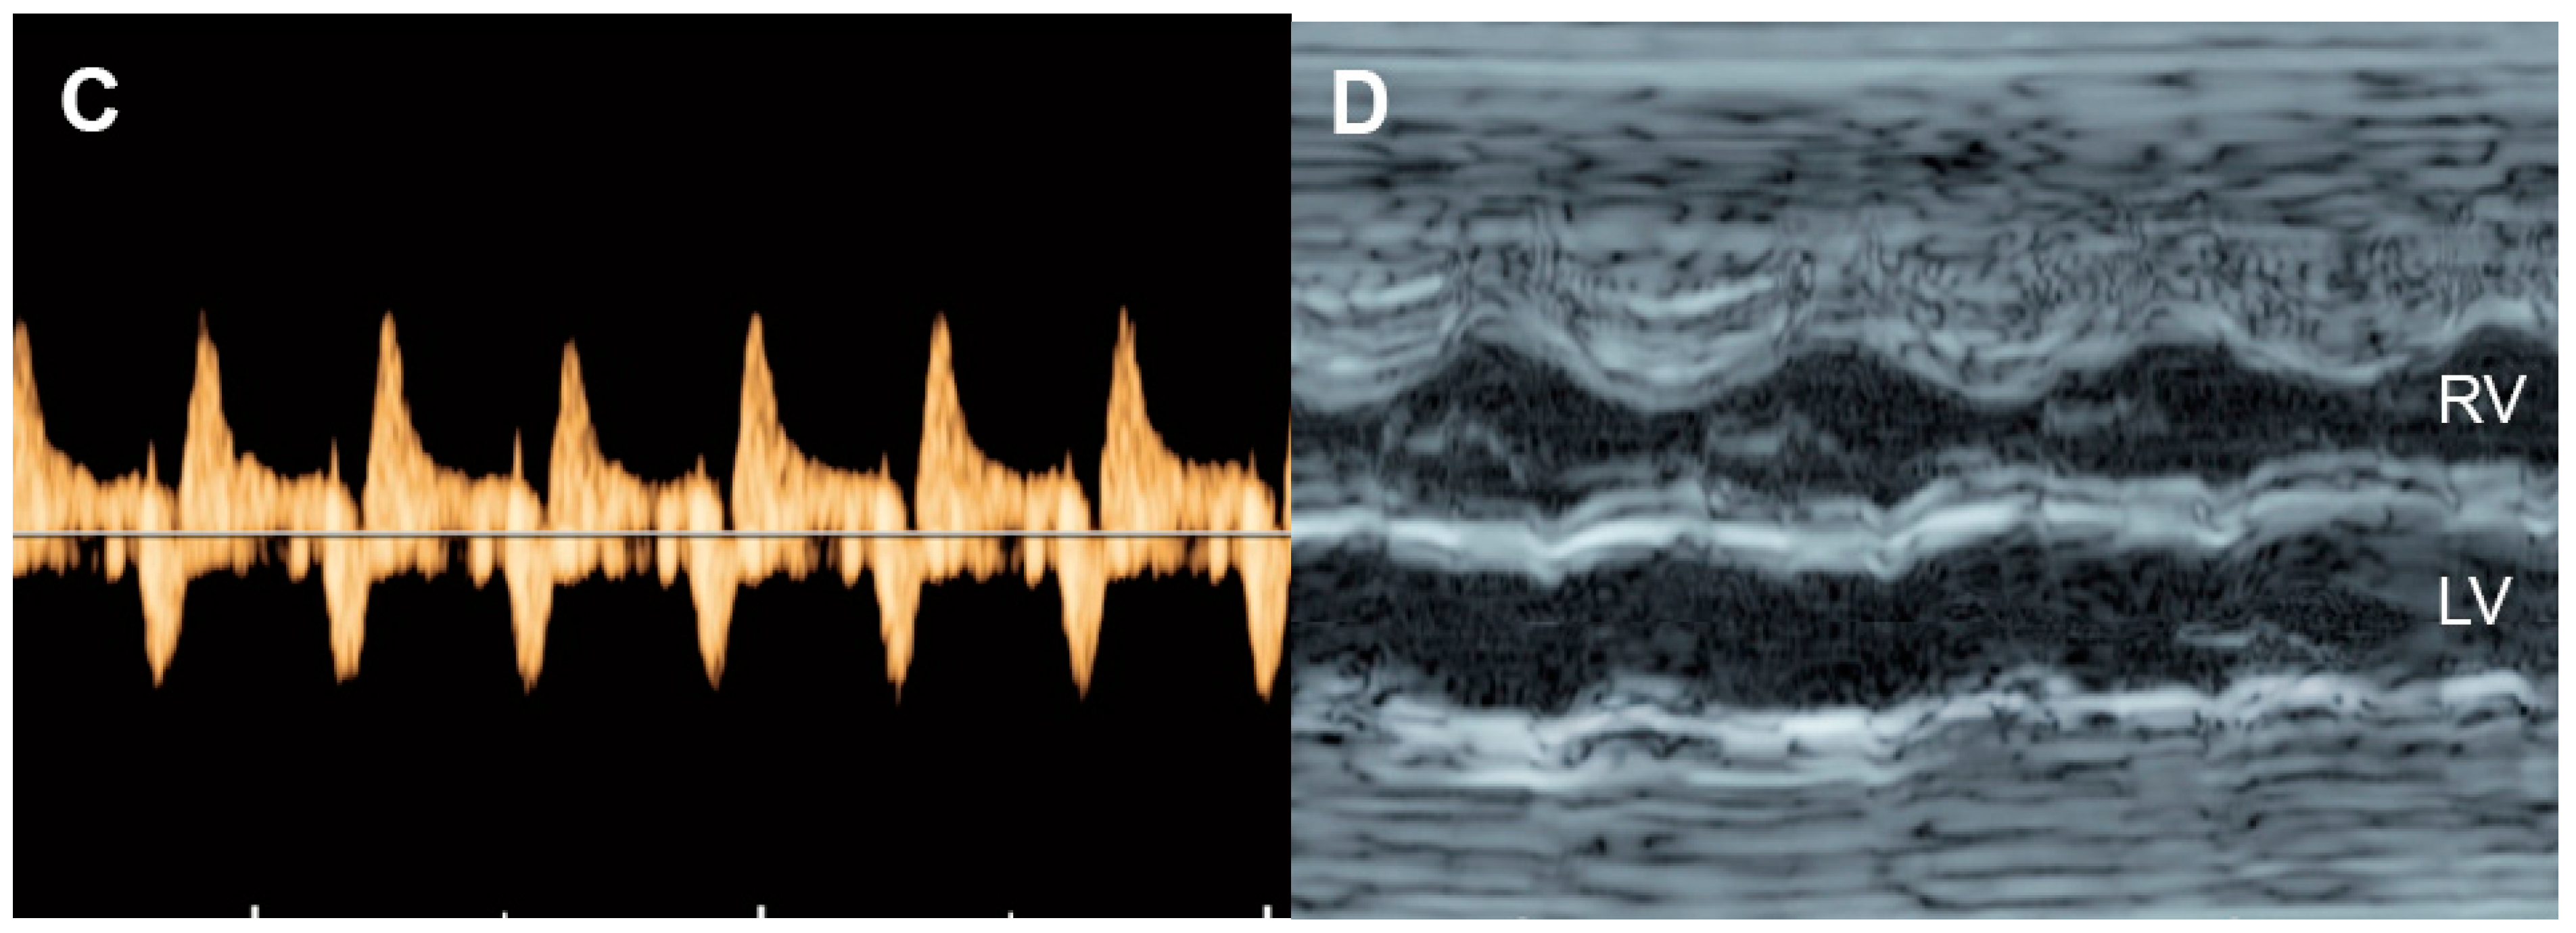

4.1. Ventricular Shortening Fraction (SF)

| Shortening fraction | Decreased (<28%) | Systolic dysfunction |

| Increased | Reduced afterload/increased contractility | |